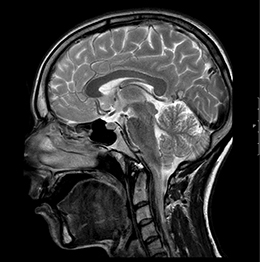

In der MRT, die auch als Kernspintomographie bezeichnet wird, kommen keine radioaktiven Strahlen zum Einsatz. Die Bildgebung erfolgt durch Signale, die für den Menschen unschädlich sind. Mit Hilfe eines außerordentlich starken Magnetfeldes werden die Wasserstoffkerne in den Molekülen der verschiedenen Gewebe des Körpers wie Kompassnadeln ausgerichtet. Durch Änderung des Magnetfeldes und wiederholter Sendung von Frequenzimpulsen schwingen sie in ihre ursprüngliche Lage wieder zurück, wobei sie ihrerseits Signale aussenden, die in einem Hochleistungscomputer in Schnittbilder umgewandelt werden.

Die MRT ist hinsichtlich der Darstellbarkeit von verschiedenen Organen, Gefäßen, Bändern und Gelenken vielen anderen heute in der Radiologie zur Verfügung stehenden bildgebenden Verfahren überlegen. Insbesondere Entzündungsherde und vitale Tumoren können mit der MRT häufig besser erkannt werden als mit anderen Verfahren.